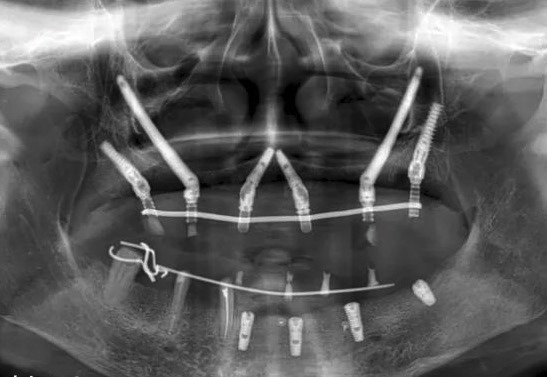

穿顴種植牙是上頜骨嚴重骨吸收情況下的一種有效替代治療方法,也可被用于上頜骨缺損的修復(fù)治療,既避免了大量的植骨手術(shù),且能明顯縮短種植治療周期。

效果展示

1. 骨量充足的 1 區(qū)及雙側(cè)缺骨的 2、3 區(qū):建議 2-4 顆傳統(tǒng)軸向種植體位于 1 區(qū),雙側(cè) 2 或 3 區(qū)各加一顆顴骨種植體。

2. 骨量充足的 1 區(qū)及一側(cè)缺骨的 2、3 區(qū):建議缺骨側(cè) 2、3 區(qū)一顆顴骨種植體,對側(cè) 2、3 區(qū)及 1 區(qū)采用常規(guī)種植體。

3. 缺骨的 1 區(qū)及骨量充足的 2、3 區(qū):一顆顴骨前種植體加后方常規(guī)種植體即可。

4. 1、2、3 區(qū)均缺骨:4 顆顴骨種植體即可。